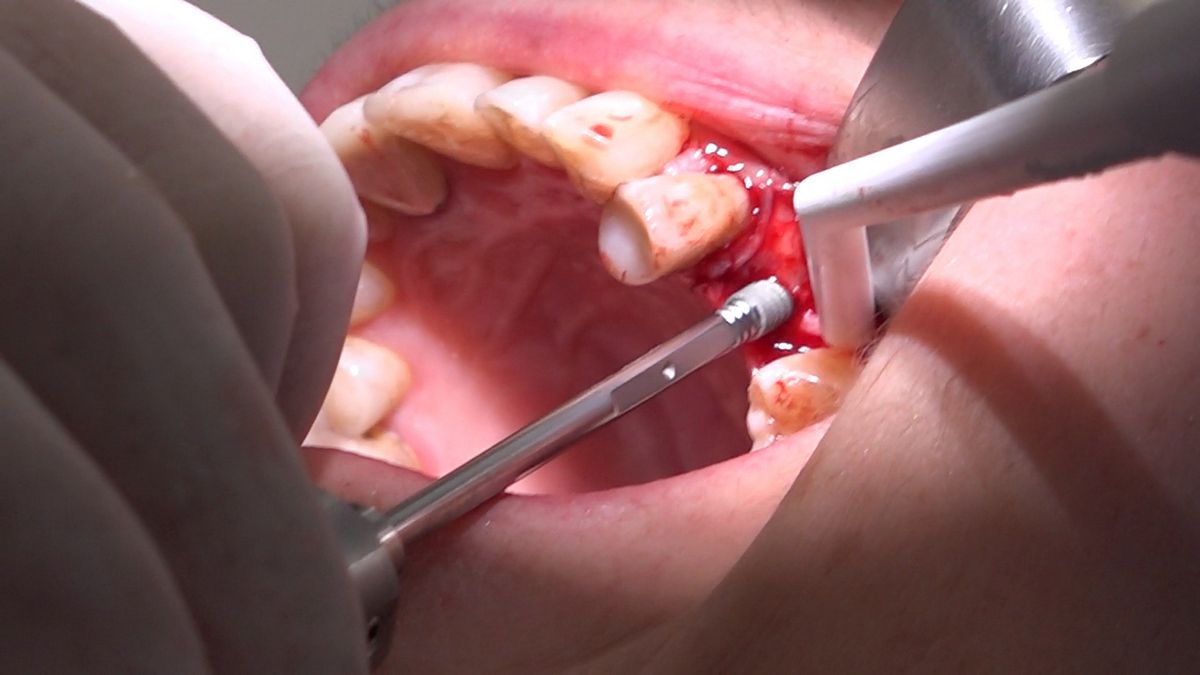

PRACTICULUM IMPLANTOLOGII - SEZON X - SESJA 4 - GRUPA B